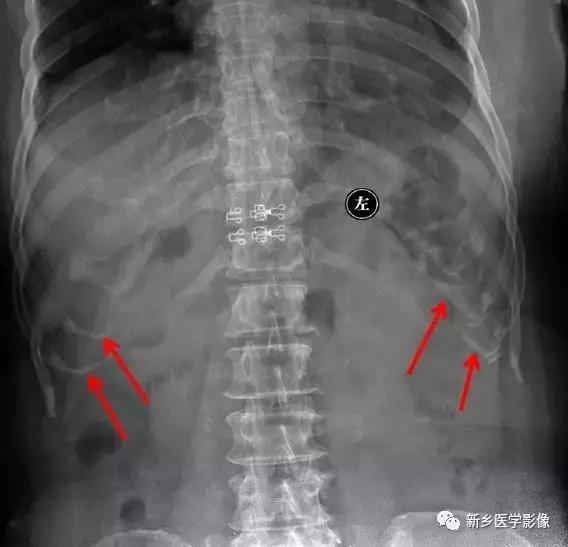

6、动脉钙化动脉瘤